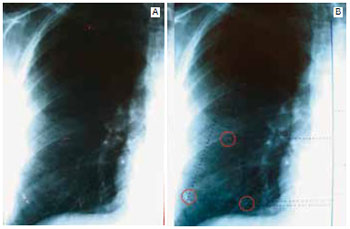

Medidas variáveis: medidas dos clipes de titânio em relação aos pontos fixos de referência (Figura 10).

Figura 10 - A: Em vermelho: a linha média do tórax anterior, o ponto entre o 1/3 medial e os 2/3 laterais da borda inferior da clavícula, e o ponto central de cada um dos clipes (3) utilizados para marcação do retalho dermolipoglandular da mama direita; B: Linhas interrompidas ilustrando a medida vertical e horizontal de cada clipe (círculos vermelhos).

- Distância vertical: medida do ponto de referência clavicular ao ponto médio de cada clipe visualizado, em cada lado.

- Distância horizontal: medida da linha média do tórax anterior ao ponto médio de cada clipe visualizado, em cada lado.

O presente estudo utilizou metodologia original e de baixo custo para estudar este propósito. Por meio de radiografia simples de tórax pôde-se acompanhar a movimentação do retalho dermolipoglandular marcado com 3 clipes de titânio, bem como avaliar a influência da cinta muscular peitoral na sustentação do retalho mamário no pós-operatório precoce e tardio. Com relação às medidas fixas ou pontos de referência do tórax anterior, utilizou-se a transição do 1/3 medial e 2/3 laterais da clavícula como parâmetro para as medidas verticais dos clipes. Este foi escolhido em virtude de ser um ponto constante no tórax anterior, localizado em projeção bem vertical em relação ao retalho marcado. A linha média do tórax, necessária para as medidas horizontais dos clipes, não poderia seguir a linha média da coluna vertebral, pois pequena rotação da paciente para um dos lados durante a realização da radiografia alteraria as medidas bilateralmente, prejudicando as comparações entre os exames. Por isso, em cada filme radiográfico, a linha média do tórax anterior foi definida identificando-se o ponto médio entre as epífises mediais das clavículas, o qual frequentemente não coincidia com a linha média da coluna vertebral, posteriormente. Tendo em vista o formato dos clipes utilizados para marcar os retalhos (10 x 1 mm), bem como a posição que eles estavam no momento do exame, foi padronizado realizar as medidas a partir do ponto médio de cada clipe. Assim, evitaram-se vieses de marcação causados pela simples rotação de um clipe, sem que o mesmo tivesse alterado sua distância vertical ou horizontal como um todo.